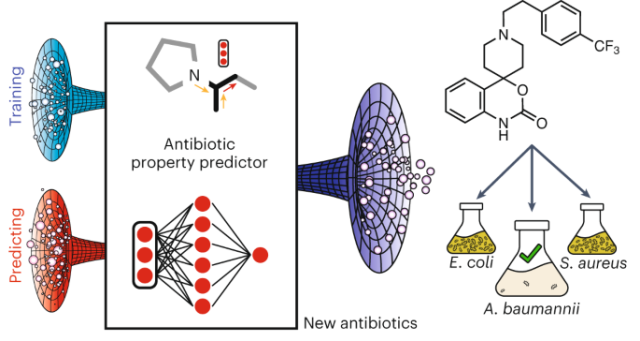

this is a really interesting paper:

Deep learning-guided discovery of an antibiotic targeting Acinetobacter baumannii

nature.com/articles/s41589-023…

But the abstract already reveals the secret sauce: it's not the model, it's screening 7500 molecules in vitro and then training a model based on that. It's always the data, not the particular model architecture, that enables breakthroughs.

Deep learning-guided discovery of an antibiotic targeting Acinetobacter baumannii - Nature Chemical Biology

Using a neural network trained on bacterial growth inhibition data, in silico prediction of molecules with activity against Acinetobacter baumannii led to the identification of the narrow-spectrum abaucin, which perturbs lipoprotein trafficking.Nature